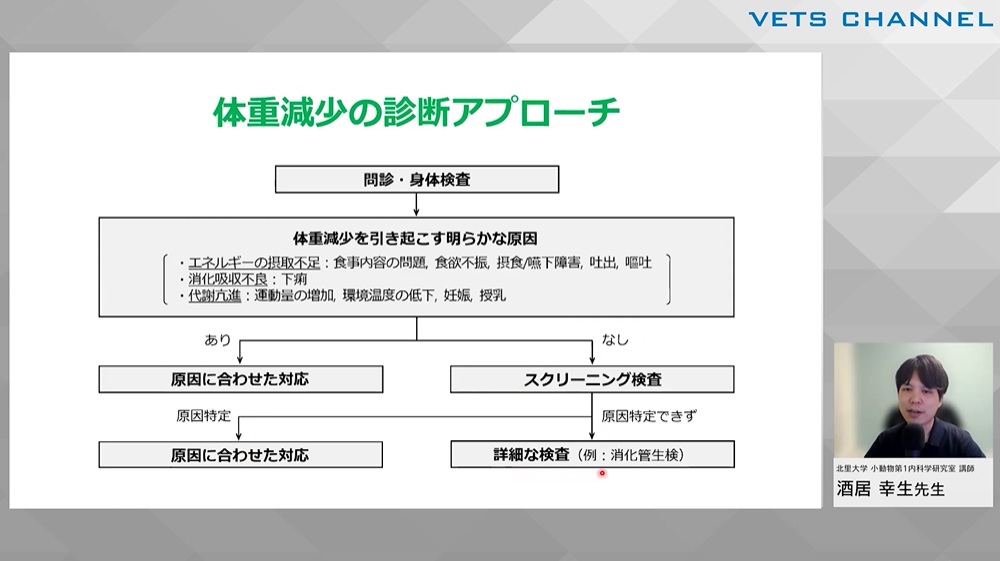

細かな変化を見落とさない!体重減少から疑う疾患アプローチ「消化・吸収不良」

- セミナー

- 内科全般

- 消化器科

- 腫瘍科

- 犬

- 猫

酒居 幸生先生 (北里大学)

75分

2025/08/22